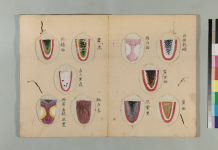

經曰:診脈之道,觀人勇怯,

肌肉皮膚,能知其情,以為診法也。

人之色,白不及黑,嫩不及蒼,薄不及厚。

而況肥人濕多,瘦人火多,白者肺氣虛,黑者腎氣足。

形色既殊,髒腑亦異。外証雖同,治法迥別。

素問に基づいた望診と脈診で

人を診ていくことの大事さを説いております。